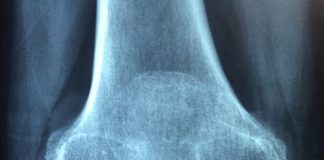

Reumatyczne zapalenie stawów

Reumatyczne zapalenie stawów, w medycynie nazwane raczej zapaleniem reumatoidalnym to choroba autoimmunologiczna. Oznacza to, że główne źródło jej tkwi w procesach immunologicznych. Układ odpornościowy,...